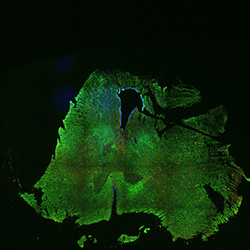

An anatomical analysis of the developing human midbrain from 6 post-conceptional weeks (PCW) to 22 PCW reveals increased tissue complexity, characterized by the emergence of dopaminergic nuclei, as highlighted by immunofluorescence analysis for tyrosine hydroxylase (TH).

Merged

6PCW human midbrain